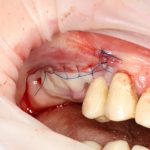

Простой синуслифтинг. Часть I.